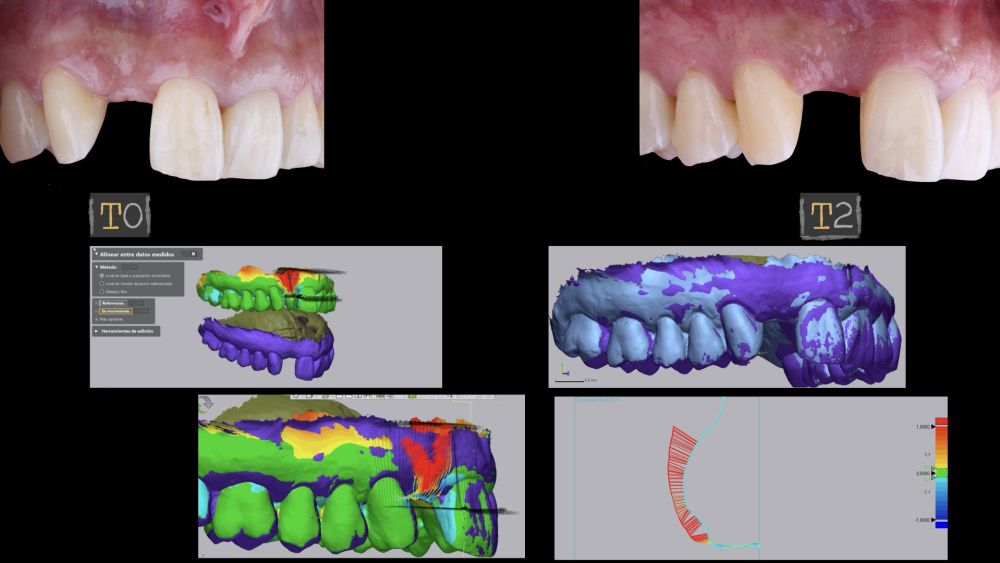

1.3 Mediciones digitales del tejido blando vestibular aumentado

El sitio donde se realizó la cirugía (implante 1.2), junto a su arco completo, se escanearon utilizando un escáner óptico intraoral en diferentes periodos de tiempo; tres semanas antes de la cirugía (T0), inmediatamente después de la cirugía (T1) y al mes y medio tras la cirugía (T2). Los modelos digitales generados se exportaron y guardaron como archivos STL para posteriormente importarlos al software de análisis de imágenes (Geomagic® Control X™; 3D Systems, Rockhill, SC). Se realizó el análisis de los cambios de espesor preoperatorios (T0) frente a los postoperatorios (T1 y T2). Estos cambios de espesor longitudinales se analizaron en la cara vestibular de la corona implantosoportada con la función “3D Compare”, lo que permitió crear un mapa de colores tras la superposición de los modelos, para analizar cuantitativamente las variaciones ocurridas en las áreas de intervención. El mapa de colores oscila entre +3 mm hasta -3 mm, con una tolerancia de ± 0,15 mm y se interpreta de la siguiente manera: áreas verdes corresponden a un alineamiento perfecto de los modelos; los colores rojos, naranjas y amarillos se interpretan como una ganancia de volumen y los colores azul oscuro y claro representan respectivamente una pérdida volumétrica (Figuras 8 y 9). Posteriormente, se diseñó una región de interés rectangular para el estudio del área de intervención donde se evaluaron los cambios lineales de la mucosa periimplantaria (Figuras 8 y 9). La extensión horizontal de la región de interés abarcó ambas papilas (mesial y distal) cubriendo el contorno marginal de la corona implantaría hasta la superficie marginal de los dientes adyacentes. Para informar los resultados de interés, se identificaron puntos en el plano horizontal previamente diseñado en la cara vestibular del implante, comenzando desde mesial y extendiéndose 0,5 mm de distancia en dirección distal. Los valores positivos indicaron que los tejidos periimplantarios estaban ubicados más bucalmente (> grosor) mientras que los negativos denotaron que los tejidos periimplantarios estaban ubicados más a palatino (< grosor).

El resultado clínico final fue satisfactorio cumpliendo las demandas estéticas del paciente. Los tejidos blandos estaban morfológicamente y dimensionalmente estables sin ningún signo de inflamación. Sin embargo, los cambios del tejido blando periimplantario (espesor volumétrico vestibular) fueron demostrados de manera cualitativa y cuantitativa (Figuras 8 y 9). En el postoperatorio inmediato (T1), la ganancia media obtenida al comparar T0 frente a T1 fue de 0,88 ± 0,15 mm con un incremento máximo de 1,1 mm. Al comparar T0–T2, se observó una ganancia media de 0,73 ± 0,23 mm. Es decir, se ha producido una contracción de volumen de 0,16 mm desde la colocación del injerto (T1) hasta pasado un mes y medio (T2).

En el presente caso clínico, se colocó un injerto de tejido conectivo desepitelizado por vestibular y oclusal obteniendo mayor espesor mucoso y mayor altura del tejido supracrestal. La literatura describe las ventajas de realizar aumentos de tejidos blandos periimplantarios siendo beneficiosos no solo para minimizar la recesión de la mucosa vestibular sino que también, ayudan a la estabilidad ósea periimplantaria 9,23–25. El estudio de Thoma y cols. con un periodo de seguimiento de hasta 3 años, observaron cambios mínimos en el grosor del tejido blando periimplantario en los sitios de implantes previamente injertados con una membrana xenogénica (-0,2 mm) frente a un injerto de tejido conectivo subepitelial (-0,1 mm)26. Además, encontraron mayores aumentos de espesor mucoso con el uso de injerto de conectivo autólogo frente al uso del sustituto xenogénico (0,3 mm en promedio más alto para el uso injerto conectivo autólogo). Sin embargo, los datos obtenidos en nuestro trabajo para el espesor mucoso no se pueden comparar con los datos de Thoma y cols, ya que nuestro trabajo tiene un periodo de seguimiento corto (un mes y medio aproximadamente) y solo analiza el cambio producido entre T0–T1 y T0–T2, no analizando el espesor inicial de tejido mucoso periimplantario26. Si Podemos observar en nuestro estudio que entre T1 y T2 el injerto de conectivo sufre contracciones durante su cicatrización (en promedio 0,16 mm).